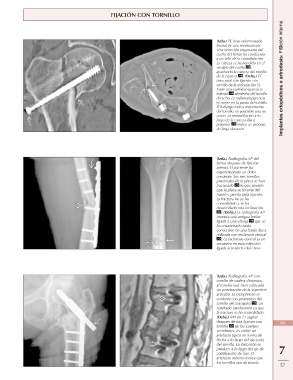

Page 15 - Manaster - Musculoesquelético 2: Enfermedades No Traumáticas